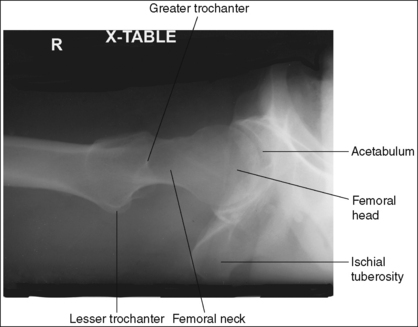

Hip: Anteroposterior Projection

The following image analysis criteria are used for all adult and pediatric hip and pelvis images and should be considered when completing the analysis for each hip and pelvis projection presented in this chapter (Box 7-1).

• Visibility of hip and pelvis details. An optimal kVp technique, as shown in Table 7-1, sufficiently penetrates the proximal femur, hip, and pelvic structures and provides a contrast scale necessary to visualize the pelvic and femoral details. Use a grid to absorb the scatter radiation produced by the proximal femur, hip, and pelvis, providing a higher contrast image. To obtain optimal density, set a manual milliampere-seconds (mAs) level based on the patient's part thickness or choose the appropriate automatic exposure control (AEC) chamber when recommended. AEC is contraindicated if the patient has hip or pelvic hardware or orthopedic apparatus.

See Figure 7-1 and Box 7-2.

Contrast and density are adequate to demonstrate the pericapsular gluteal, iliopsoas, and obturator fat planes.

• Fat planes on AP hip and pelvic projections. When evaluating AP hip and pelvis projections, the reviewer not only analyzes the bony structures but also studies the placement of the soft tissue fat planes. Four fat planes are of interest on AP hip projections, and their visualization aids in the detection of intraarticular and periarticular disease: obturator internus fat plane, which lies within the pelvic inlet next to the medial brim; the iliopsoas fat plane, which lies medial to the lesser trochanter; the pericapsular fat plane, which is found superior to the femoral neck; and the gluteal fat plane, which lies superior to the pericapsular fat plane (Figure 7-2).

The pelvis demonstrates an AP projection. The ischial spine is aligned with the pelvic brim, the sacrum and coccyx are aligned with the symphysis pubis, and the obturator foramen is open.

• An AP projection of the hip is obtained by placing the patient supine on the imaging table with the legs extended (Figure 7-3). To ensure that the pelvis is not rotated, judge the distances from the anterior superior iliac spines (ASISs) to the imaging table. The distances on each side should be equal.

• Detecting pelvis rotation. Rotation on an AP hip projection is initially detected by evaluating the relationship of the ischial spine and the pelvic brim, the alignment of the sacrum and coccyx with the symphysis pubis, and the degree of obturator foramen demonstration. If the patient was rotated toward the affected hip, the ischial spine is demonstrated without pelvic brim superimposition, the sacrum and coccyx are not aligned with the symphysis pubis but are rotated away from the affected hip, and the obturator foramen is narrowed (see Image 1). If the patient has been rotated away from the affected hip, the ischial spine is not aligned with the pelvic brim but is demonstrated closer to the acetabulum, the sacrum and coccyx are not aligned with the symphysis pubis, but are rotated toward the affected hip, and the obturator foramen is widened (see Image 2).

The femoral neck is demonstrated without foreshortening, the greater trochanter is in profile laterally, and the lesser trochanter is superimposed by the femoral neck.

• Accurate leg positioning. To demonstrate an AP hip projection with the femoral neck shown without foreshortening and the greater trochanter in profile, the patient's leg should be internally rotated until the foot is angled 15 to 20 degrees from vertical and the femoral epicondyles are positioned parallel with the imaging table (Figure 7-4; see Figure 7-1). A sandbag or tape may be needed to help the patient maintain this internal leg rotation.

• Poor leg positioning. The relationship of the patient's leg to the imaging table determines how the femoral neck and trochanters are shown on an AP hip projection. In general, when patients are relaxed, their legs and feet are externally (laterally) rotated. On external rotation, the femoral neck declines posteriorly (toward the table) and is foreshortened on an AP hip projection. Increased external rotation increases the degree of posterior decline and foreshortening of the femoral neck on the image. If the patient's leg is externally (laterally) rotated enough to position the foot at a 45-degree angle and an imaginary line connecting the femoral epicondyles at a 60- to 65-degree angle with the imaging table, the femoral neck is demonstrated on end and the lesser trochanter is demonstrated in profile (Figure 7-5; see Image 3). If the patient's leg is positioned with the foot placed vertically and an imaginary line connecting the femoral epicondyles at approximately a 15- to 20-degree angle with the imaging table, the lesser trochanter is demonstrated in partial profile and the femoral neck is only partially foreshortened (see Image 4).

• Positioning for a fractured or dislocated proximal femur. When a patient has a dislocated or fractured proximal femur, the leg should not be internally rotated but left as is. Forced internal rotation of a dislocated or fractured proximal femur may injure the blood supply and nerves that surround the injured area. Because the patient's leg is not internally rotated when a fracture is suspected, the resulting AP hip projection may demonstrate the femoral neck with some degree of foreshortening and the lesser trochanter without femoral shaft superimposition (see Image 5).

The femoral head or neck is at the center of the exposure field. The acetabulum, greater and lesser trochanters, femoral head and neck, and half of the sacrum, coccyx, and symphysis pubis are included within the collimated field. Any orthopedic apparatus located at the hip are included in their entirety.

• A perpendicular central ray is centered 1.5 inches (4 cm) distal to the midpoint of a line connecting the ASIS and superior symphysis pubis, to center the hip joint in the center of the exposure field, and a perpendicular central ray is centered 2.5 inches (6.25 cm) distal to the midpoint of a line connecting the ASIS and superior symphysis pubis to place the femoral neck in the center of the exposure field (Figure 7-6). Center the IR to the central ray and open the longitudinal collimation enough to include the ASIS and any hip orthopedic apparatus. Transversely collimate to the patient's midsagittal plane and within 0.5 inch (1.25 cm) of the lateral hip skin line. Including half of the sacrum, coccyx, and symphysis pubis within the exposure field provides a way to evaluate pelvic rotation.

• A 10- × 12-inch (24- × 30-cm) IR placed lengthwise should be adequate to include all the required anatomic structures. A larger IR and lower centering point may be necessary to include hip orthopedic apparatus (Figure 7-7).

• Gonadal shielding. Use gonadal shielding on all male patients. Female patients should be shielded, although it is important that no pelvic anatomy be covered by the shield. It is not uncommon for patients with hip fractures to have an associated pelvic fracture. Remember that a shield placed on top of the patient will be greatly magnified.